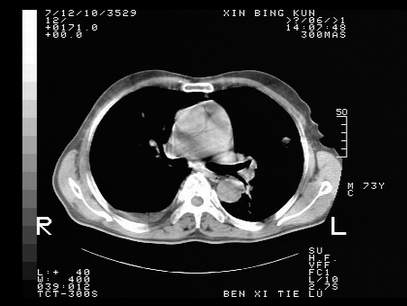

标题: CT10820:男,73岁,病史肺TB,现病史肺炎,直肠CA术后 [打印本页]

标题: CT10820:男,73岁,病史肺TB,现病史肺炎,直肠CA术后

双肺间质改变,依据病史双肺多发结节灶考虑转移,少量胸水.

1.两肺结核.2.两肺多发转移瘤.3右侧少量胸腔积液4.主动脉钙化.

双肺多发结节及条片状致密影,右侧少量胸腔积液。临床:直肠ca术后,肺tb病史。综合考虑:1 双肺转移!2 继发性肺结核合并感染!

此人病史较复杂,原有肺结核,直肠癌术后。肺部病灶形态亦呈多形性。因此,不可仅以一种病来解释肺部的病变。双肺多发的类圆形结节灶,结合病史还是首先考虑转移瘤,而双肺其余病灶还需结合化验室检查,结核或肺部感染在无其它检查资料的情况下不好排除。还是那句话----放射科医生不是开照像馆的,我们也是医生,看片一定要多结合临床及其它检查资料。要当一名合格的放射科医生,并不比当一名临床医生容易,我们可别把自已不当医生看。

两肺多发结节影,并见滋养动脉与其相连,考虑 两肺转移. 右侧胸腔积液考虑胸膜转移.

左肺上叶下叶背段,右肺中下叶见多发斑片状、条索状高密度影,兵变周围小结节影形成“树芽”样改变。 左肺上叶舌段近前胸壁处及右肺中叶内侧段见结节影。右侧胸膜腔内见液体密度区。纵隔内未见明确增大淋巴结。考虑左肺上叶舌段近前胸壁处及右肺中叶转移瘤可能性大。两肺继发型肺结核。右侧胸腔积液。